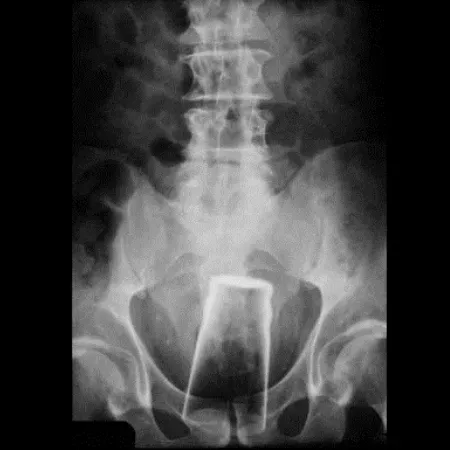

(3)파인트잔:당시에는 좋은 생각이었던거 같다.